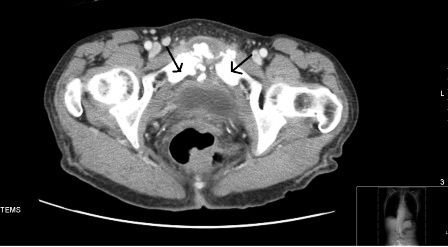

Chest x-ray film was normal. ECG showed sinus tachycardia. CT of abdomen with contrast showed markedly increased sclerotic changes and fragmentation in the pubic symphysis associated with soft tissue thickening and small abscess formation, consistent with pubic osteomyelitis (Figure). CT-guided bone biopsy showed marrow replacement by fibrous and granulation tissue, consistent with chronic osteomyelitis. Echocardiogram was unremarkable. Patient refused surgical debridement. She was treated with 8 weeks of intravenous vancomycin, with a good clinical response. Her ESR decreased to 30 mm/h and CRP to 5.28 mg/L.

Clinical features of pelvic osteomyelitis include fever, pelvic pain worsened with walking, localized tenderness over the pubic symphysis and a wide-based waddling gait. Complications include abscess formation, pelvic instability, pubic diastasis, and bladder perforation. Pubic osteomyelitis needs to be differentiated from osteitis pubis, which refers to bony destruction of margins of the symphysis pubis along with severe pelvic pain and waddling gait often the result of an inflammatory and not infectious process. The diagnosis depends on a positive blood/bone culture and histopathology with compatible radiographic findings in an appropriate clinical setting.

MRI is more sensitive than CT. CT is preferable when evaluating for osseous sequestra, delineating abscesses, or sinus tracts or for planning intervention. MRI can demonstrate marrow edema as early as within 3 to 5 days of infection and helps with diagnosing acute osteomyelitis.